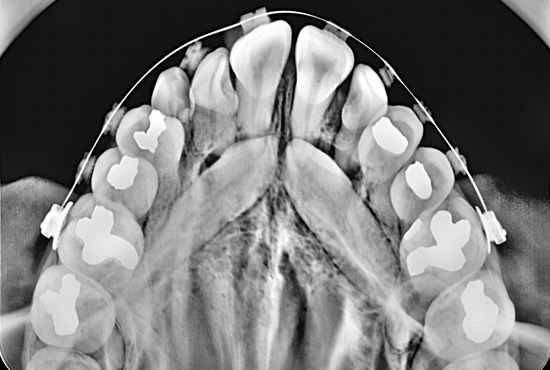

La Radiografía Intraoral Digital captura imágenes precisas y de alta resolución de áreas específicas dentro de la boca, útil para identificar caries, infecciones o problemas en las raíces dentales.